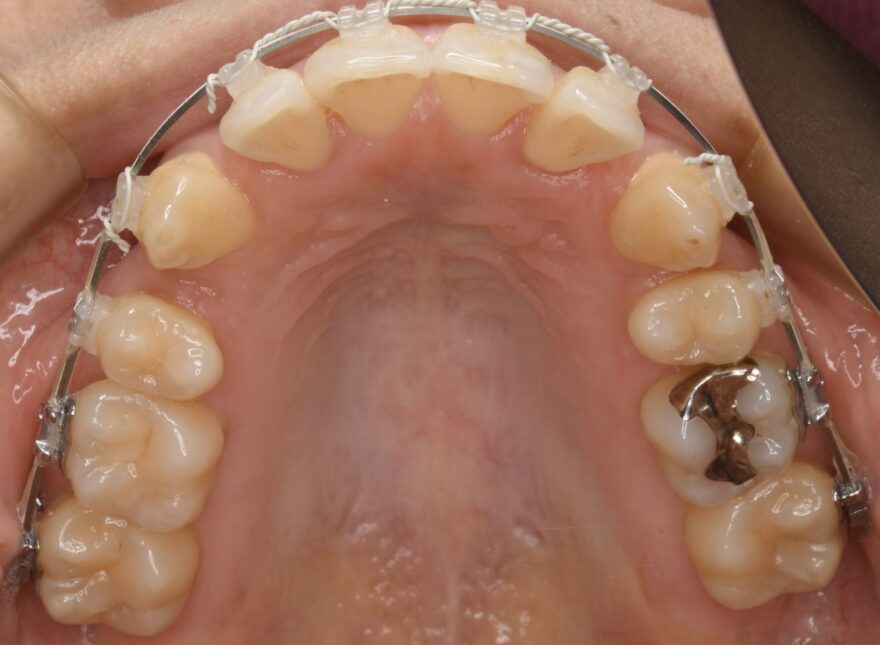

初診時の口腔内写真

上下の前歯のガタガタが気になります。

左上の2番目の前歯が、内側に引っ込んでいます。